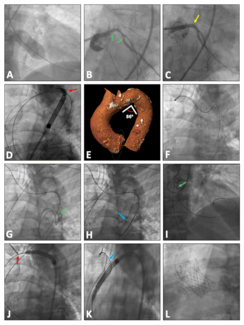

An 82-year-old male patient with severe, symptomatic aortic stenosis was referred for transcatheter aortic valve implantation.

An 83-year-old man with symptomatic severe aortic valve stenosis with severe ventricular dysfunction underwent valvuloplasty and percutaneous coronary intervention before being referred for transcatheter aortic valve replacement.